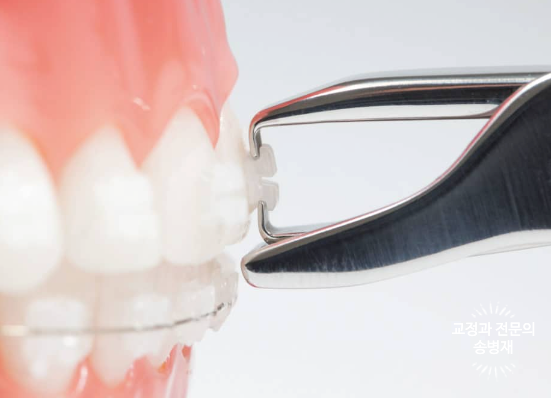

브라켓이라고 하는 교정장치는 치아를 잡고 움직이기 위해 치아에 부착됩니다.

보통 2년이라는 시간 동안 부착되어 있어야 하기 때문에 치아와 매우 단단히 부착이 되죠.

이러한 브라켓을 교정치료 종료 후 제거할 때 치아에 힘이 가해지게 되고, 이때 실금이 생길 수 있습니다.

이러한 실금 발생을 최소화하기 위해서는 교정장치 제거 시 최대한 조심스럽고, 부드러운 힘을 이용하여 제거하여야 하고,

무엇보다 치아 하나하나를 본인 치아라고 생각하는, 조심성 많은 좋은 치과의사를 만나시는 게 중요합니다.^^

하지만 아무리 조심해도 어쩔 수 없이 발생하는 경우가 있습니다.